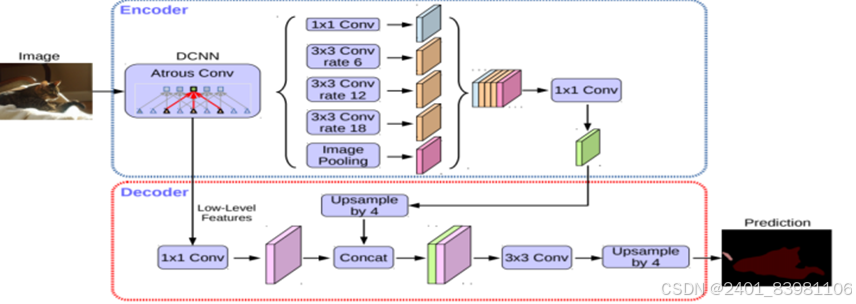

传统的语义分割任务存在一些问题:CNN中连续的池后缩减采样导致空间分辨率下降;尺度检测需要重新缩放和聚合特征图,这会导致过多的计算工作量。图像分类任务需要保证空间变换是不变的,因此引入了Deeplab结构

现状:较为完善;如使用孔卷积空间金字塔池化模块(ASPP)(张新锋等提出了一种端到端的舌像分割算法,该算法采用空洞卷积和空间金字塔池化模块,扩大了网络的感受野,从多个 尺度学习舌像特征,同时采用CRF全连接层细化舌体边缘的特征信息,实验结果表明 PA 值达到了 99.85%),将深度卷积神经网络(DCNNs)和全连接的条件随机场 (CRFs)相结合的方法进行舌图像分割,具有较高的分割精度,mIoU达95.41%。

( DeepLabv3+网络结构图)